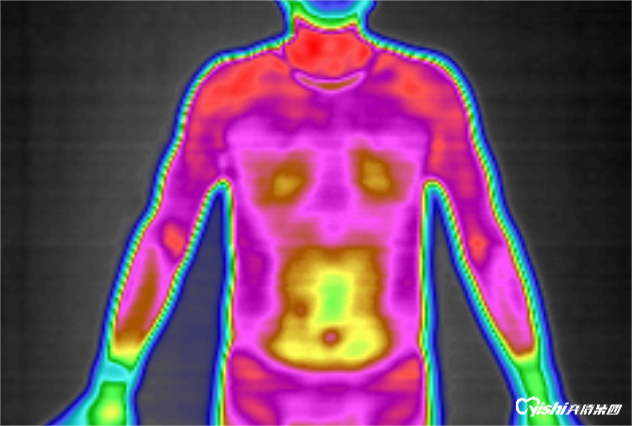

代谢紊乱,看你是否中招了?红外热成像一看便知!

近年来,各种代谢性疾病的患病率不断攀升,严重影响着人们的身体健康与生命安全。尽早发现并及时进行干预治疗,可以大幅度延缓其进程,对于降低心脑血管疾病及相关并发症的发病率及死亡率具有重要意义。什么是代谢性疾病?代谢性疾病是指机体内糖、脂肪、蛋白质等物质代谢紊乱引发的一类疾病,主要包括糖尿病、